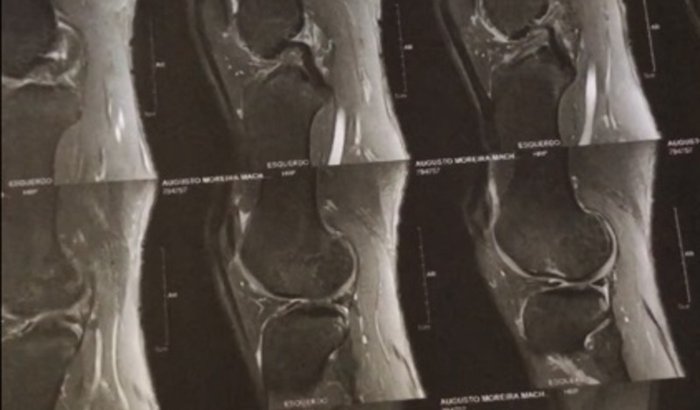

meu nome é Augusto só atleta cristão de skate   amador durante um treino de skate tive uma torção no joelho rompido 50% do LCA  tiver lesão no menisco e também na cartilagem preciso fazer uma cirurgia para voltar a andar de skate não tenho ver tudo

meu nome é Augusto só atleta cristão de skate   amador durante um treino de skate tive uma torção no joelho rompido 50% do LCA  tiver lesão no menisco e também na cartilagem preciso fazer uma cirurgia para voltar a andar de skate não tenho convênio médico esto sem patrocínio, Espero que possa voltar logo  me ajudam Compartilhe o vídeo eu posso voltar logo anda  skate Deus abençoe esta  cirugia custa 10, mil reis , Peço a Deus força está sendo difícil passar por isso mais Deus fiel ,🙏🖤 meu pix 91344862 Augusto Moreira Machado Nubank